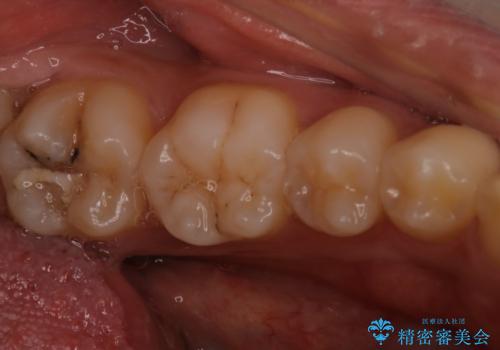

また矯正後、患者様の希望で

メタルインレーをセラミックインレーにやりかえさせていただき、さらに綺麗に仕上がりました。

- 天然歯を削ります

- 硬い素材は天然歯を傷つけてしまう場合があります

- かみ合わせや歯ぎしりが強すぎる方はセラミックが割れてしまう可能性があります

- 自費診療(保険適用外治療)となります